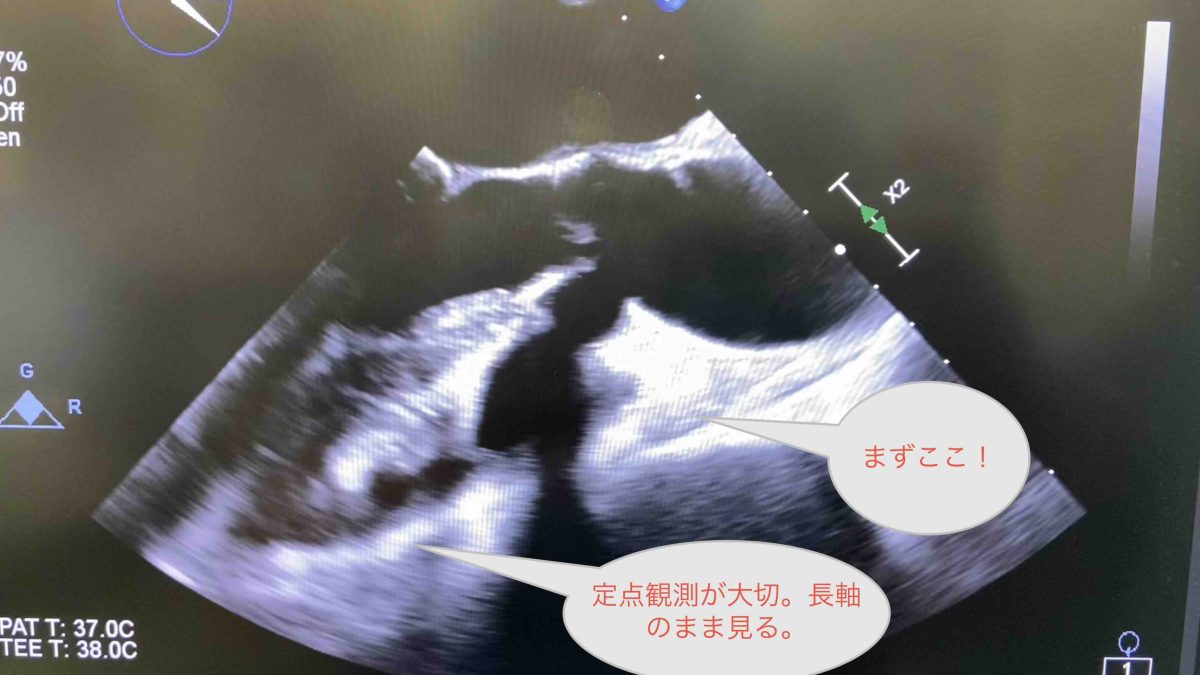

Weekly Update 保護中: TAVI 初級編4 TEE ③ TAVI本番編 デプロイ 05/15/2025 渡部功三 このコンテンツはパスワードで保護されています。閲覧するには以下にパスワードを入力してください。 パスワード: